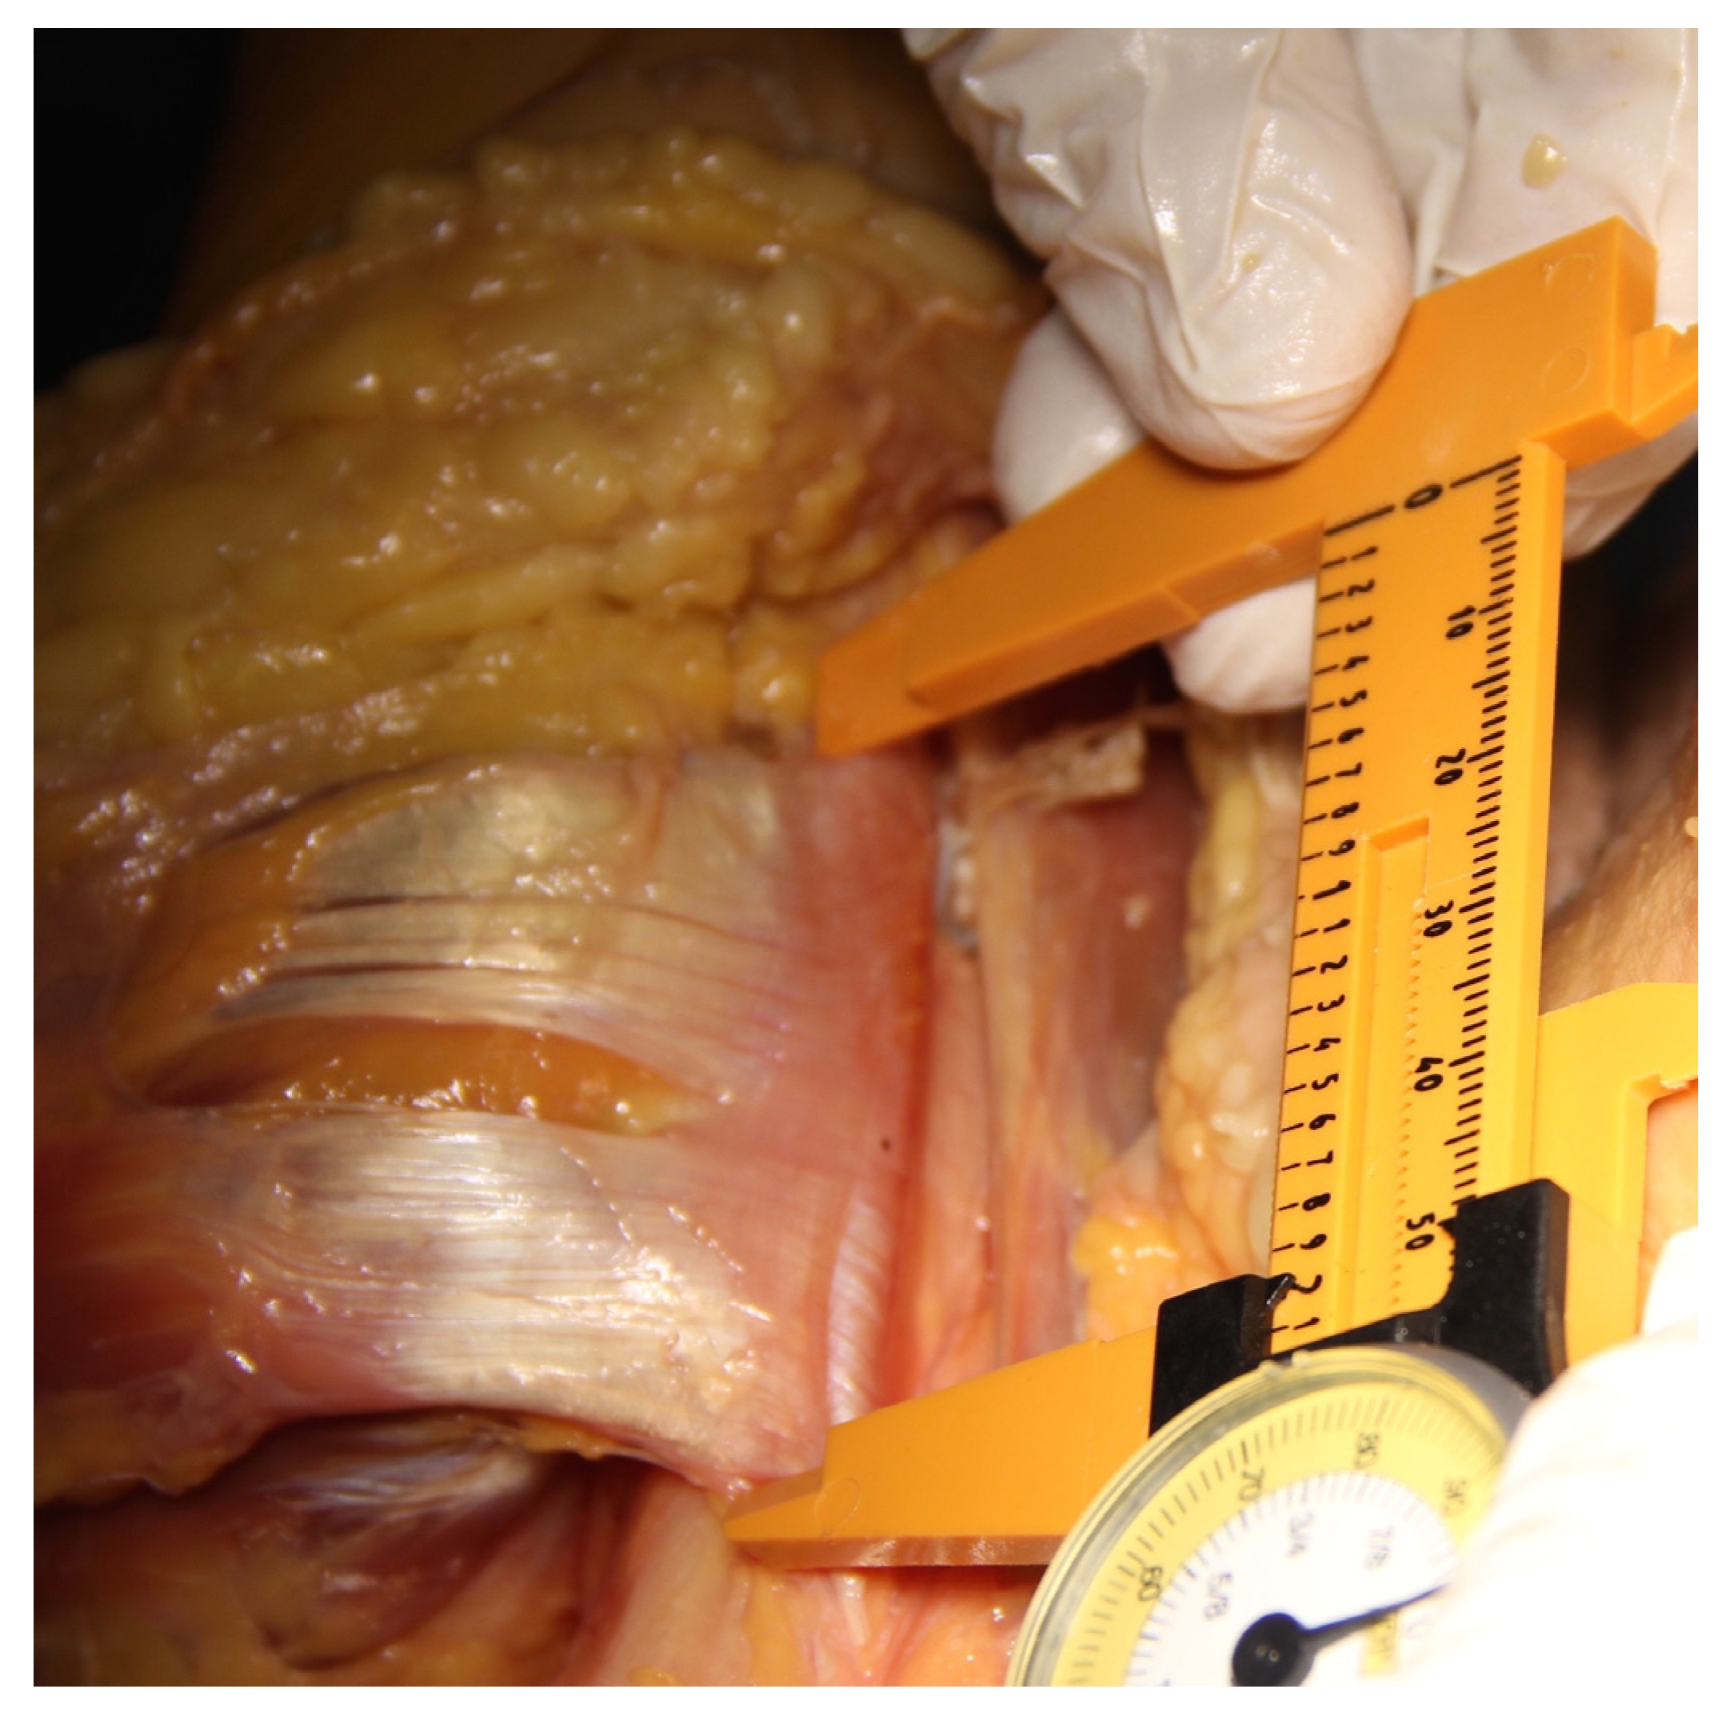

Dissection was performed following each tenodesis. The pectoralis major muscle was divided and its distal insertion everted so that the PMT could be evaluated from its deep surface (Figure 1). Manual calipers were used to measure the width of the PMT from proximal to distal at its point of insertion (PMT) (Figure 2), followed by the distance from the center of the reamed tenodesis tunnel in the anterior humeral cortex to the proximal border of the pectoralis major tendon (tunnel to PMT). The deltoid was then divided from the border of the acromion and dissection continued distally by developing the plane between the deltoid and the humerus until the axillary nerve and the cortical button were identified (Figure 1). Manual calipers were used to measure the distance from the center of the bicortical button on the posterior surface of the humerus to the axillary nerve (Button to AN). All the measurements were recorded for each specimen, including the diameter of the LHBT as measured with the tendon sizer. The 10 cadavers became available at different times, so the first 6 were studied by one primary researcher, and the last 4 were studied by another, all under the supervision and direct participation of the senior author.

Figure 1.

Anterior view of the ventral parts of a left shoulder. The pectoralis major muscle has been divided and the tendon is reflected laterally. The deltoid has been divided from the acromion and retracted laterally off the humerus to reveal the anterior branch of the axillary nerve. The close relationship between the proximal border of the pectoralis major tendon and the axillary nerve can be seen. The biceps tenodesis is seen in the bicipital groove medial to the pectoralis tendon insertion.